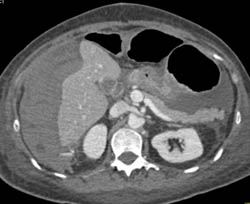

Cirrhosis With Varices